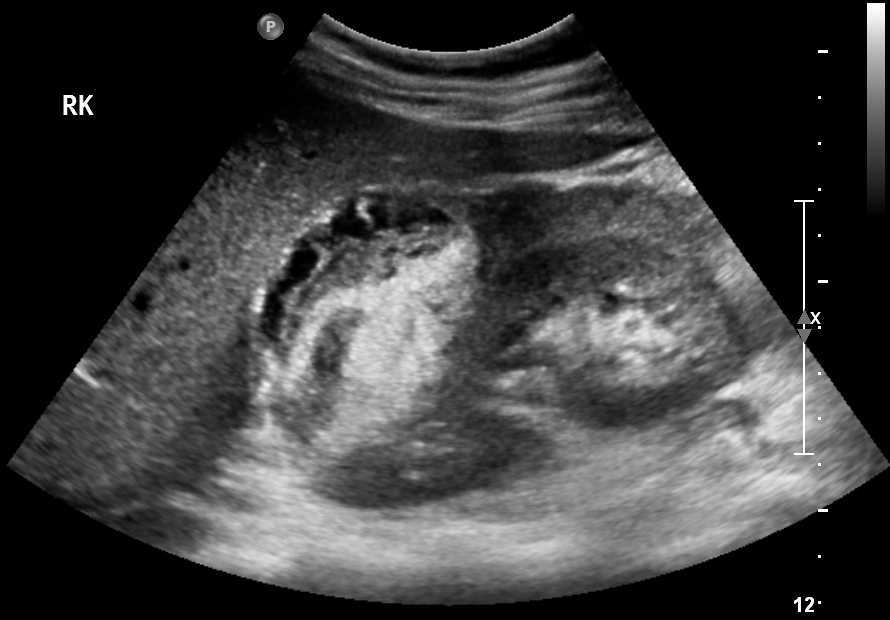

19F Hypertensive

kypokalaemia

elevated aldosterone

Juxtaglomerular Tumor (Reninoma)

Reninoma is a tumour of the cells of the juxtaglomerular apparatus that produces excessive amounts of renin, resulting in a secondary form of hyperaldosteronism, manifesting clinically with hypertension (HT) and hypokalaemia1. This renal tumour is predominant in females, with a peak incidence between the second and third decade of life and, although uncommon, it is a treatable cause of HT2. It should be suspected in any patient with refractory HT associated with hypokalaemia and high levels of aldosterone.

We present the first case of reninoma reported in Argentina in a young woman with refractory HT and hypokalaemia.